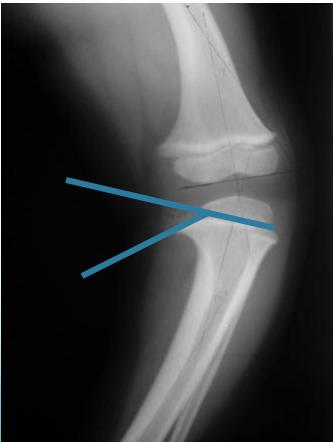

Radiological Parameters to Assess:

- Medial Physeal Slope

- Femoral-Tibial Axis

Angle measurements

Medial Physeal Slope

Femoral-Tibial Axis